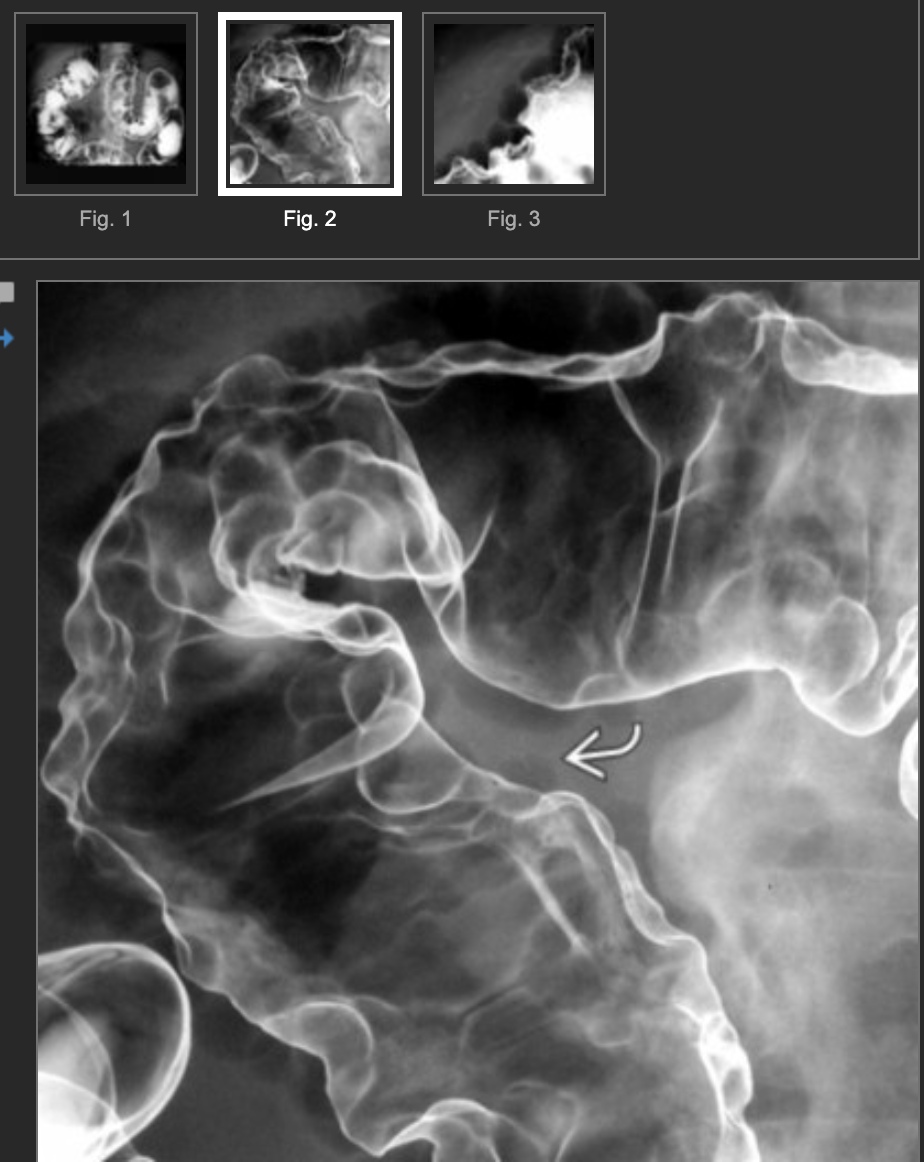

Dx? 50yo male pt w/vague abdo pain & distention & no recent Hx of instrumentation.

• Dx: idiopathic pneumatosis of the colon.

• Usually colonic.

• Ix:

• Large gas cysts in the colonic wall.

• May be mistaken for polyps if the density is not recognized.

• Must correlate w/any clinical evidence of bowel ischemia, instrumentation, etc.